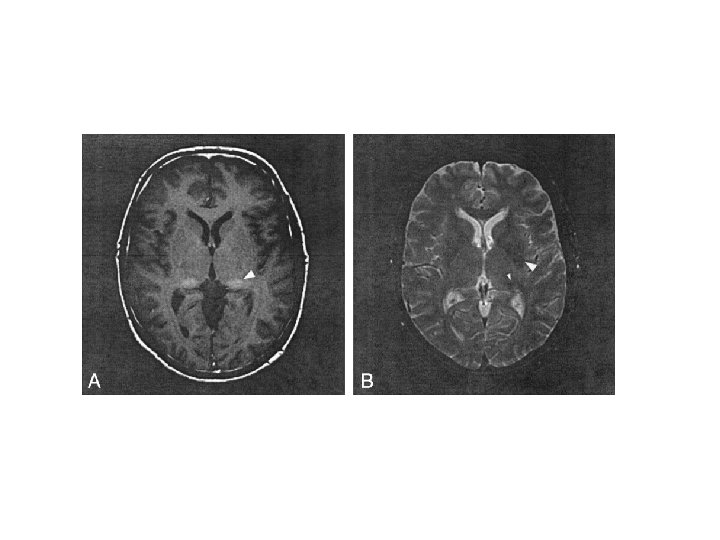

Atrofia cerebelar